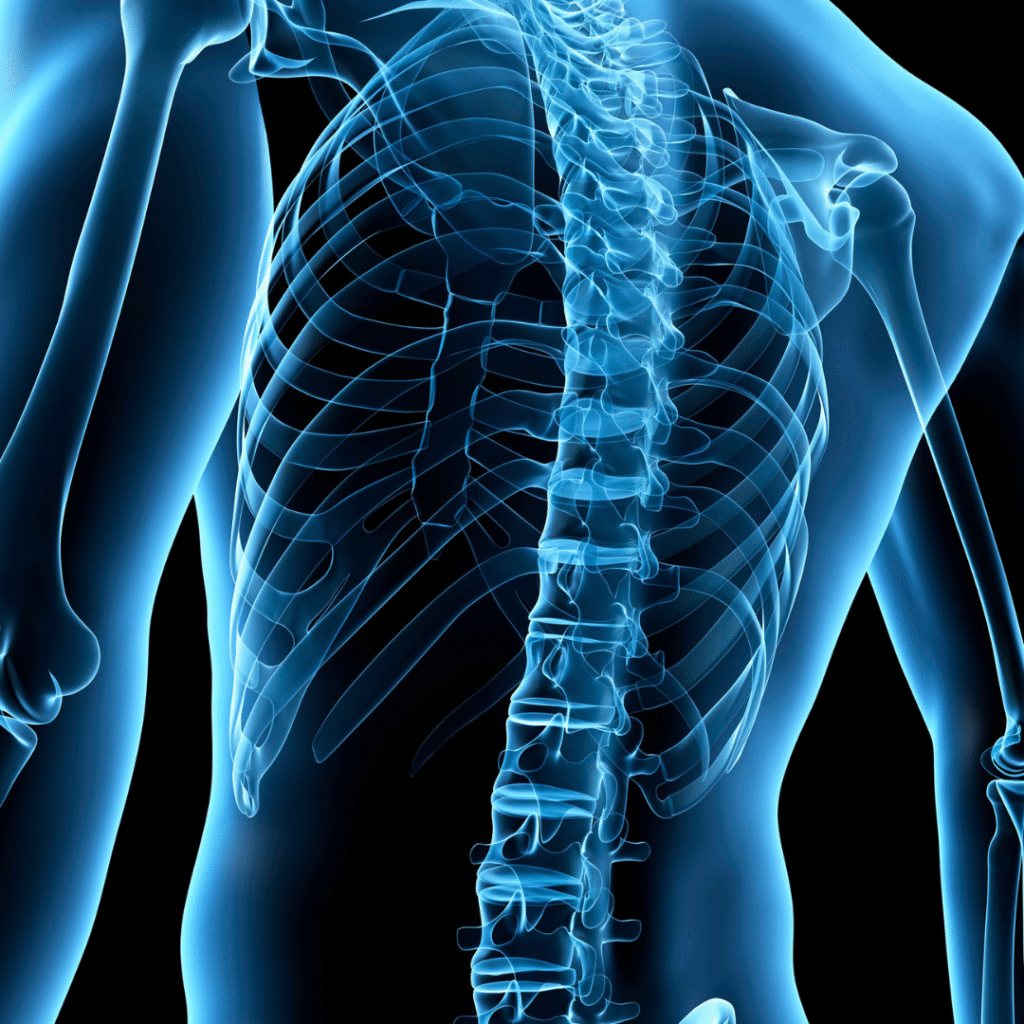

We specialize in treating back pain, neck pain, headaches, auto accident injuries, and many other conditions. Our comprehensive approach combines modern chiropractic techniques with personalized care plans designed to help you achieve optimal wellness.

At Chiropractic Connection, we believe everyone deserves to live pain-free and enjoy optimal health. Our modern facility and compassionate approach ensure you receive the highest quality care in a comfortable environment. From chronic pain management to injury recovery, we’re dedicated to helping you achieve total wellness.